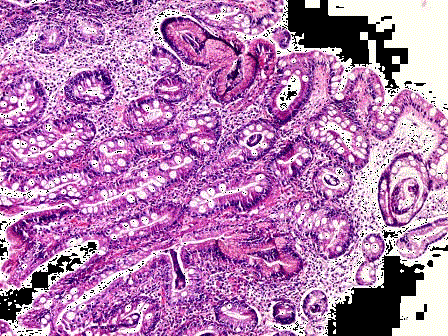

问题 胃窦部黏膜组织活检,镜下如图所示,胃黏膜发生的有关病变的描述,错误的是 ( )

选项 A.黏膜腺体中度肠上皮化生 B.这种分化上的转向,只发生于同源细胞之间 C.可分为不完全肠化和完全肠化 D.该化生对机体有利,不会发生恶变 E.该化生可恶变形成肠型腺癌

答案 D